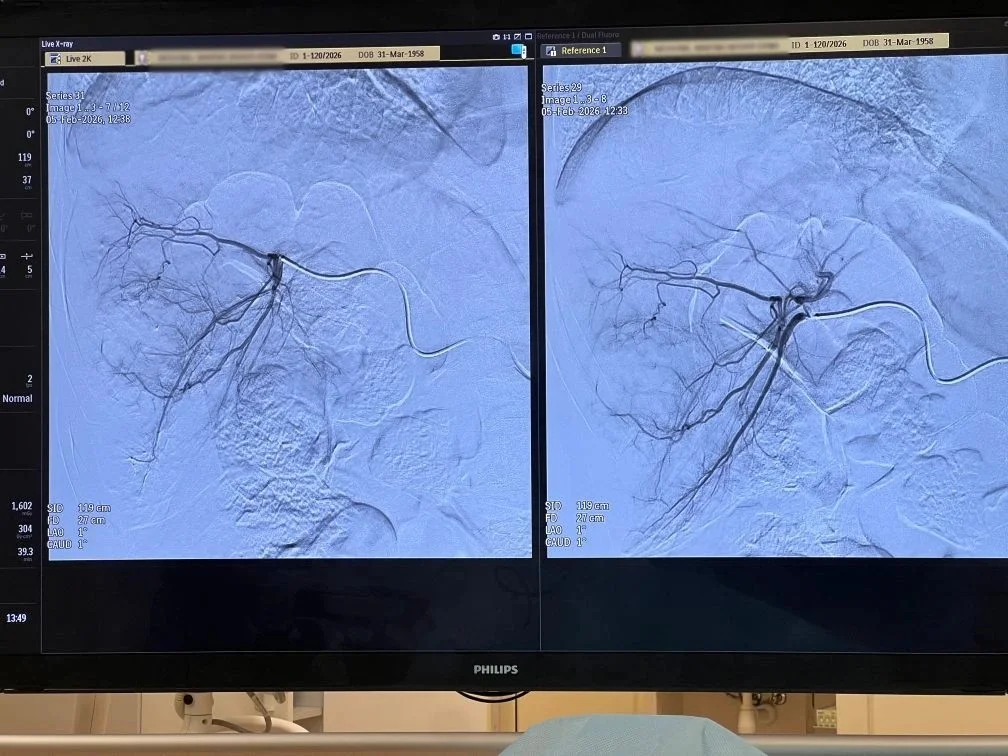

В итоге метастатические очаги у пациентки были пролечены сначала методом химиоэмболизации: медики точечно доставили в опухоль концентрированный химиопрепарат и перекрыли питающие ее артерии. После чего подвергли еще два метастаза радиочастотной абляции.

Вся операция продлилась более трех часов. Подведение электрода к очагу выполнялось под двойным контролем: с использованием рентген-диагностики сосудов, вен и артерий, а также УЗИ. Это особенно важно, поскольку вблизи опухолей проходят важные сосуды и структуры, которые такой подход позволяет сохранить.